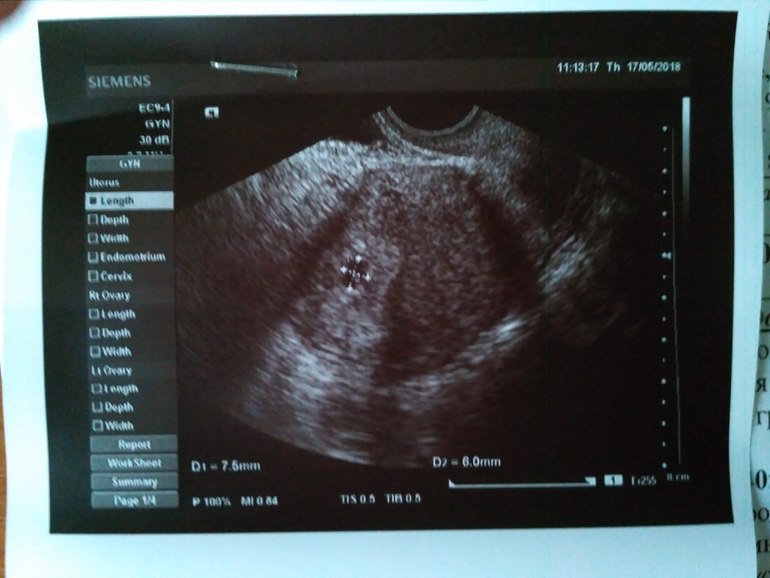

ФолликулометрияВсем привет, сходила я сегодня к гинекологу, срок 5 недель и 2 дня. Все хорошо, плодное яйцо в матке. Гинеколог подтвердила что беременность маточная, но зная какая я мнительная отправила на УЗИ) увидела я бусинку❤ узист тоже ставит срок 5-6 недель. Сдала ещё прогестерон и ТТГ. Так как в прошлую беременность принимала Утрожестан и ТТГ был повышен. До беременности был средний 2,6, решила проконтролировать. Результаты вечером. Но уже и от УЗИ и слов и гинеколога и узистки "беременность нормальная, для этого срока все отлично" на душе становится легко😍

УЗИ приложила